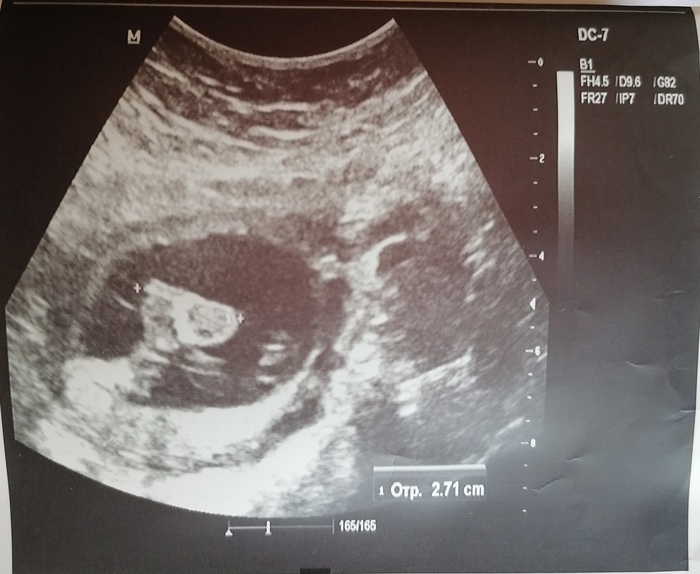

Ровно четыре месяца назад путем Экс появилась на свет Юлиана. Вес нормальный, 3750,хотя узи перед кесаревым обещало 4500)